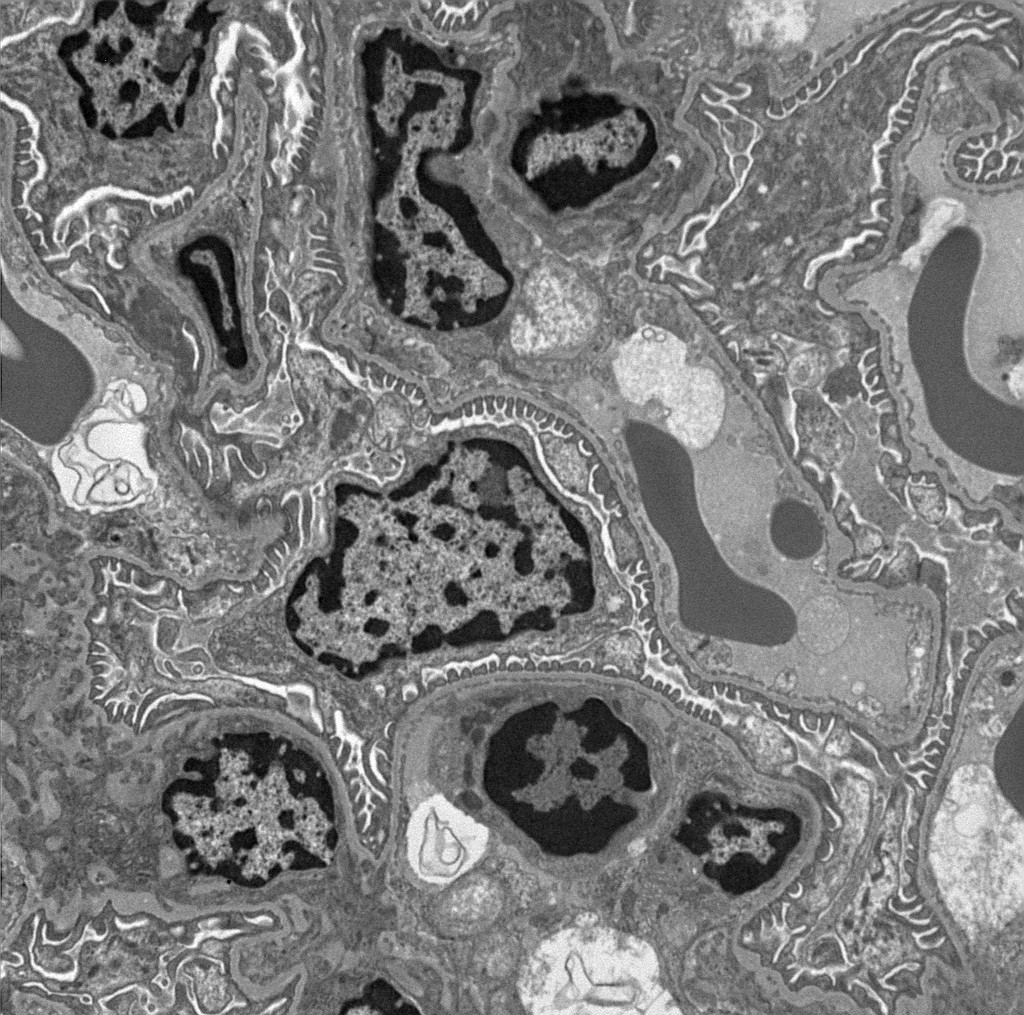

JOEL JEM-1010 Transmission Electron Microscope

Transmission Electron Microscopy of PDAC cells showing autophagic structures and mitochondria.

Viale et al., Nature, 2014.